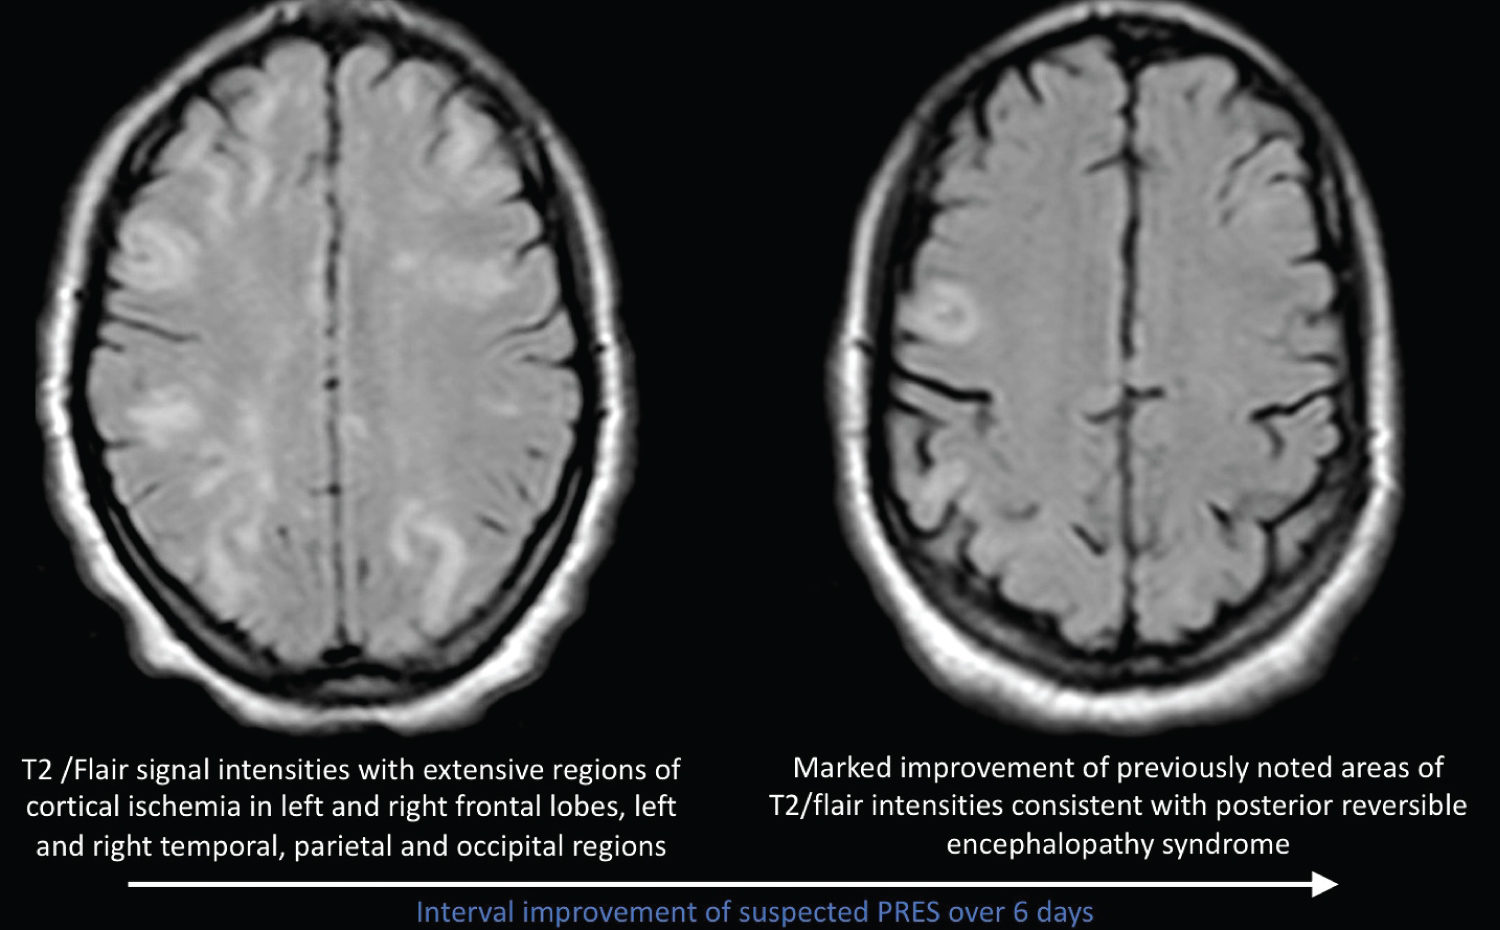

We present a 22-year-old African American female with a 3-year history of SLE diagnosed in 2017 in Georgia. Patient manifested with polyarthralgia, rash, mouth sores, alopecia and serology positive for SLE. Patient maintained on hydroxychloroquine and remained symptom free until November 2019 when she developed bilateral lower extremity edema and renal failure. Renal biopsy performed showed evidence of stage 4 lupus nephritis and was scheduled to receive 6 cycles of cyclophosphamide. Patient received first dose of cyclophosphamide on 11/26/19. 5 days later patient developed first seizure episode and subsequently developed grand mal status epilepticus requiring mechanical ventilation. MRI performed at the time with a differential diagnosis of PRES vs. lupus cerebritis. Patient received anti-hypertensives, anti-epileptics and pulse steroids with interval improvement and eventual discharge from hospital. Patient relocated to NY to continue care and was admitted evaluate need for continuation of dialysis and SLE activity. Patient was given initial pulse steroids 1g solumedrol daily for 3 days and maintained on prednisone 30 mg twice daily and hydroxychloroquine 200 mg po daily. Ds-DNA Ab level was 107 (initially > 1400 in Georgia), C3, C4 were normal. Creatinine down-trended from 2.71 to 1.54 and patient did not require hemodialysis. CT head and EEG performed upon admission were unremarkable for acute changes of seizure activity. Patient received second dose of cyclophosphamide on 1/31/20 and two days later patient developed grand mal status epilepticus and severe hypertension requiring mechanical ventilation. MRI of the brain without contrast showed significant changes compared to previous MRI consistent with vasogenic edema within bilateral occipital lobes suggestive of PRES as seen in Figure 1. Patient complained of acute blurry vision, ophthalmological eye exam was normal and the acute blurry vision was likely attributed to cortical vision loss. Patient showed interval improvement of vision and blood pressure. Repeat MRI of the brain 1 week later showed marked improvement in increased T2/flair signal intensities suggestive of resolving PRES.

Figure 1: Interval improvement of suspected PRES over 6 days. View Figure 1